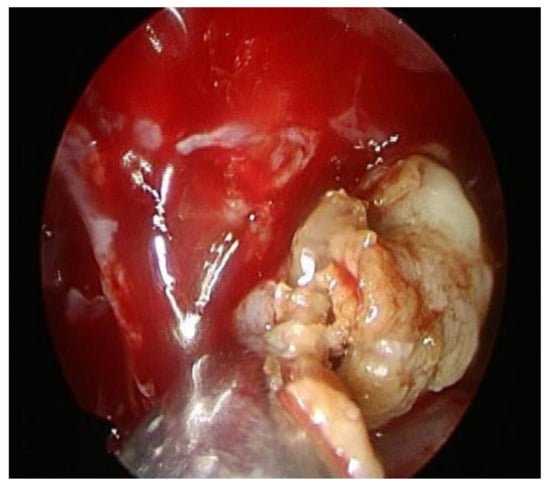

2. Case Presentation